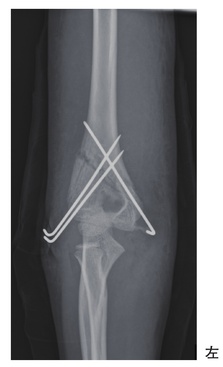

6歳の女児。公園で転倒し、骨折の診断で同日緊急手術を受けた。術後のエックス線写真を別に示す。術後の患側上肢の理学療法で正しいのはどれか。

sYhF2F6b4S

1

術後1週で筋力増強運動を開始する。

2

肘関節の運動は自動より他動を優先する。

3

術後2週で肩関節の可動域練習を開始する。

4

仮骨形成してから肘関節の可動域練習を開始する。

5

術後翌日に急激な痛みがあっても手指運動を行う。